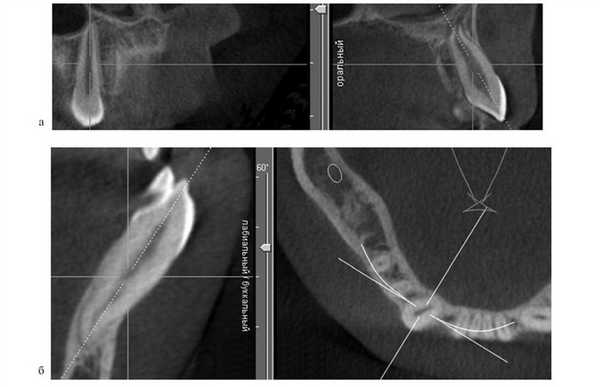

С целью устранения выраженной деформации ВЧ предложен метод создания пространства для установки расширяющих конструкций с использованием дополнительных внутрикостных опор (ортодонтических микровинтов) и эластичной тяги. Разработка данного вида ортодонтической конструкции вызвана невозможностью применения аппаратов, фиксирующихся на небе. У 4 пациентов с ВРГН при выраженной рубцовой деформации неба отмечались значительное мезиальное смещение боковых сегментов зубоальвеолярной дуги, а также дистопия и небный наклон первых и вторых премоляров; расстояние между небными поверхностями этих зубов составляло 2,5±0,3 мм. Для реализации метода проводили рентгенологическое исследование — ортопантомографию, по данным которой определяли топографию установки микровинтов. На контрольно-диагностической модели ВЧ определяли угол небного наклона премоляров относительно альвеолярного гребня, который составил 32±2,3°. Эти данные учитывали при установке микровинтов. Микровинт устанавливали под инфильтрационной анестезией в межзубном промежутке второго премоляра и первого моляра под углом, соответствующим наклону премоляра, на 3 мм ниже подвижной слизистой оболочки. К вестибулярной поверхности премоляра фиксировали ортодонтическую кнопку, от которой к головке микровинта устанавливали эластичную тягу для вестибулярного перемещения премоляра (см. рис. 1, а). Процесс перемещения премоляров длился в среднем 1,5—2,5 мес. После устранения дистопии премоляров освобождалось пространство на твердом небе для фиксации аппарата Квад-Хелликс (см. рис. 1, а). Аппарат Квад-Хелликс обеспечивал медленное расширение верхнего зубного ряда на 0,25 мм за 1 мес (рис. 1, б).

Рис. 1. Аппараты для устранения выраженной деформации верхней зубоальвеолярной дуги. а — применение ортодонтических микровинтов при резком сужении ВЧ; б — применение аппарата Квад-Хелликс.